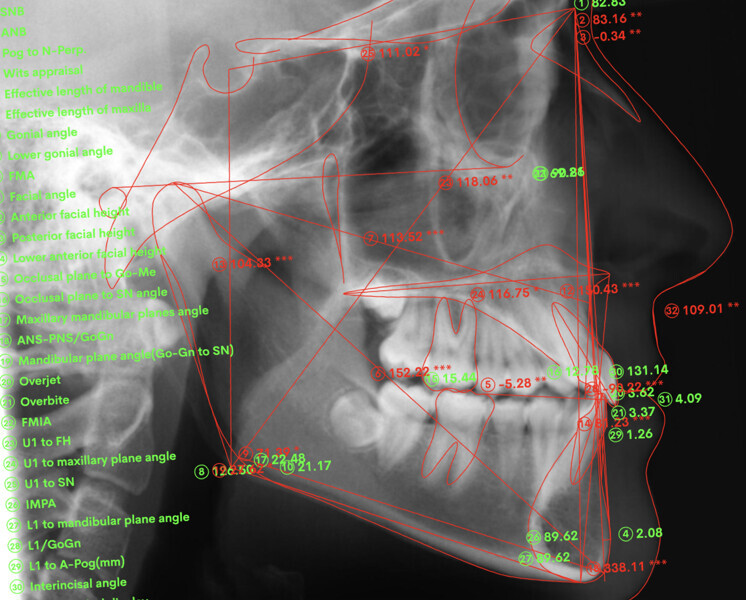

Cephalometric analysis showed normal incisor inclination (U1–PP = 112°) and slightly uprighted mandibular incisors (IMPA = 88°), consistent with dental compensation commonly observed in Class III skeletal malocclusions. Cephalometric analysis confirmed a reduced lower anterior facial height associated with a hypodivergent pattern (Figs. 13 & 14).

Superimposition of the cephalometric radiographs showed the following interesting changes due to the orthodontic treatment (Figs. 44–48):

• The inclination of the maxillary incisors with respect to the maxillary plane had changed by about 4° (U1–PP from 112° to 116°), and the inclination of the mandibular incisors with respect to the mandibular plane had changed by only 1° (IMPA from 88° to 90°), so had substantially remained stable.

• The relative extrusion of the maxillary and mandibular molars by the sectional archwire and Class III elastics had generated a slight clockwise rotation of the mandible (FMA from 19° to 21°), which had allowed an improvement of the overbite.

• The facial profile and lip support had remained stable.